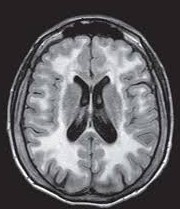

• Une leucoencéphalopathie

Une leucoencéphalopathie, ou leucopathie, désigne l’altération de la substance blanche cérébrale. Chez l’adulte, les leucopathies chroniques sont majoritairement secondaires à des maladies acquises à...